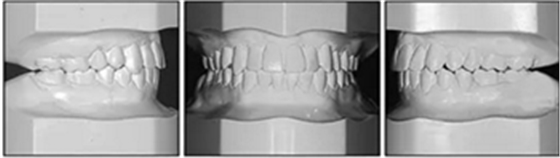

口內(nèi)相示:口腔衛(wèi)生可,下頜前牙區(qū)輕度擁擠伴齦上牙石,無齲齒、牙齦炎;開合,覆蓋5mm,休息時舌后退位,吞咽時舌前伸。

口內(nèi)相及模型:雙側磨牙、尖牙I類關系,良好的牙尖交錯關系,覆合、覆蓋正常。